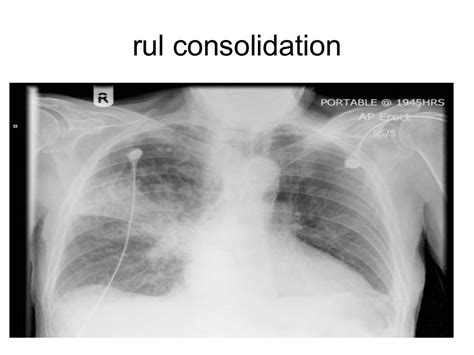

- Diagnosis of lung consolidation involves medical imaging, such as chest X-rays or CT scans, and laboratory tests, including blood cultures and sputum analysis.

The diagnosis of lung consolidation involves a combination of clinical evaluation, medical imaging, and laboratory tests. A physical examination and medical history can provide clues to the underlying cause, while chest X-rays and CT scans can help identify areas of consolidation. Laboratory tests, such as blood cultures and sputum analysis, can help identify the causative agent and guide treatment.